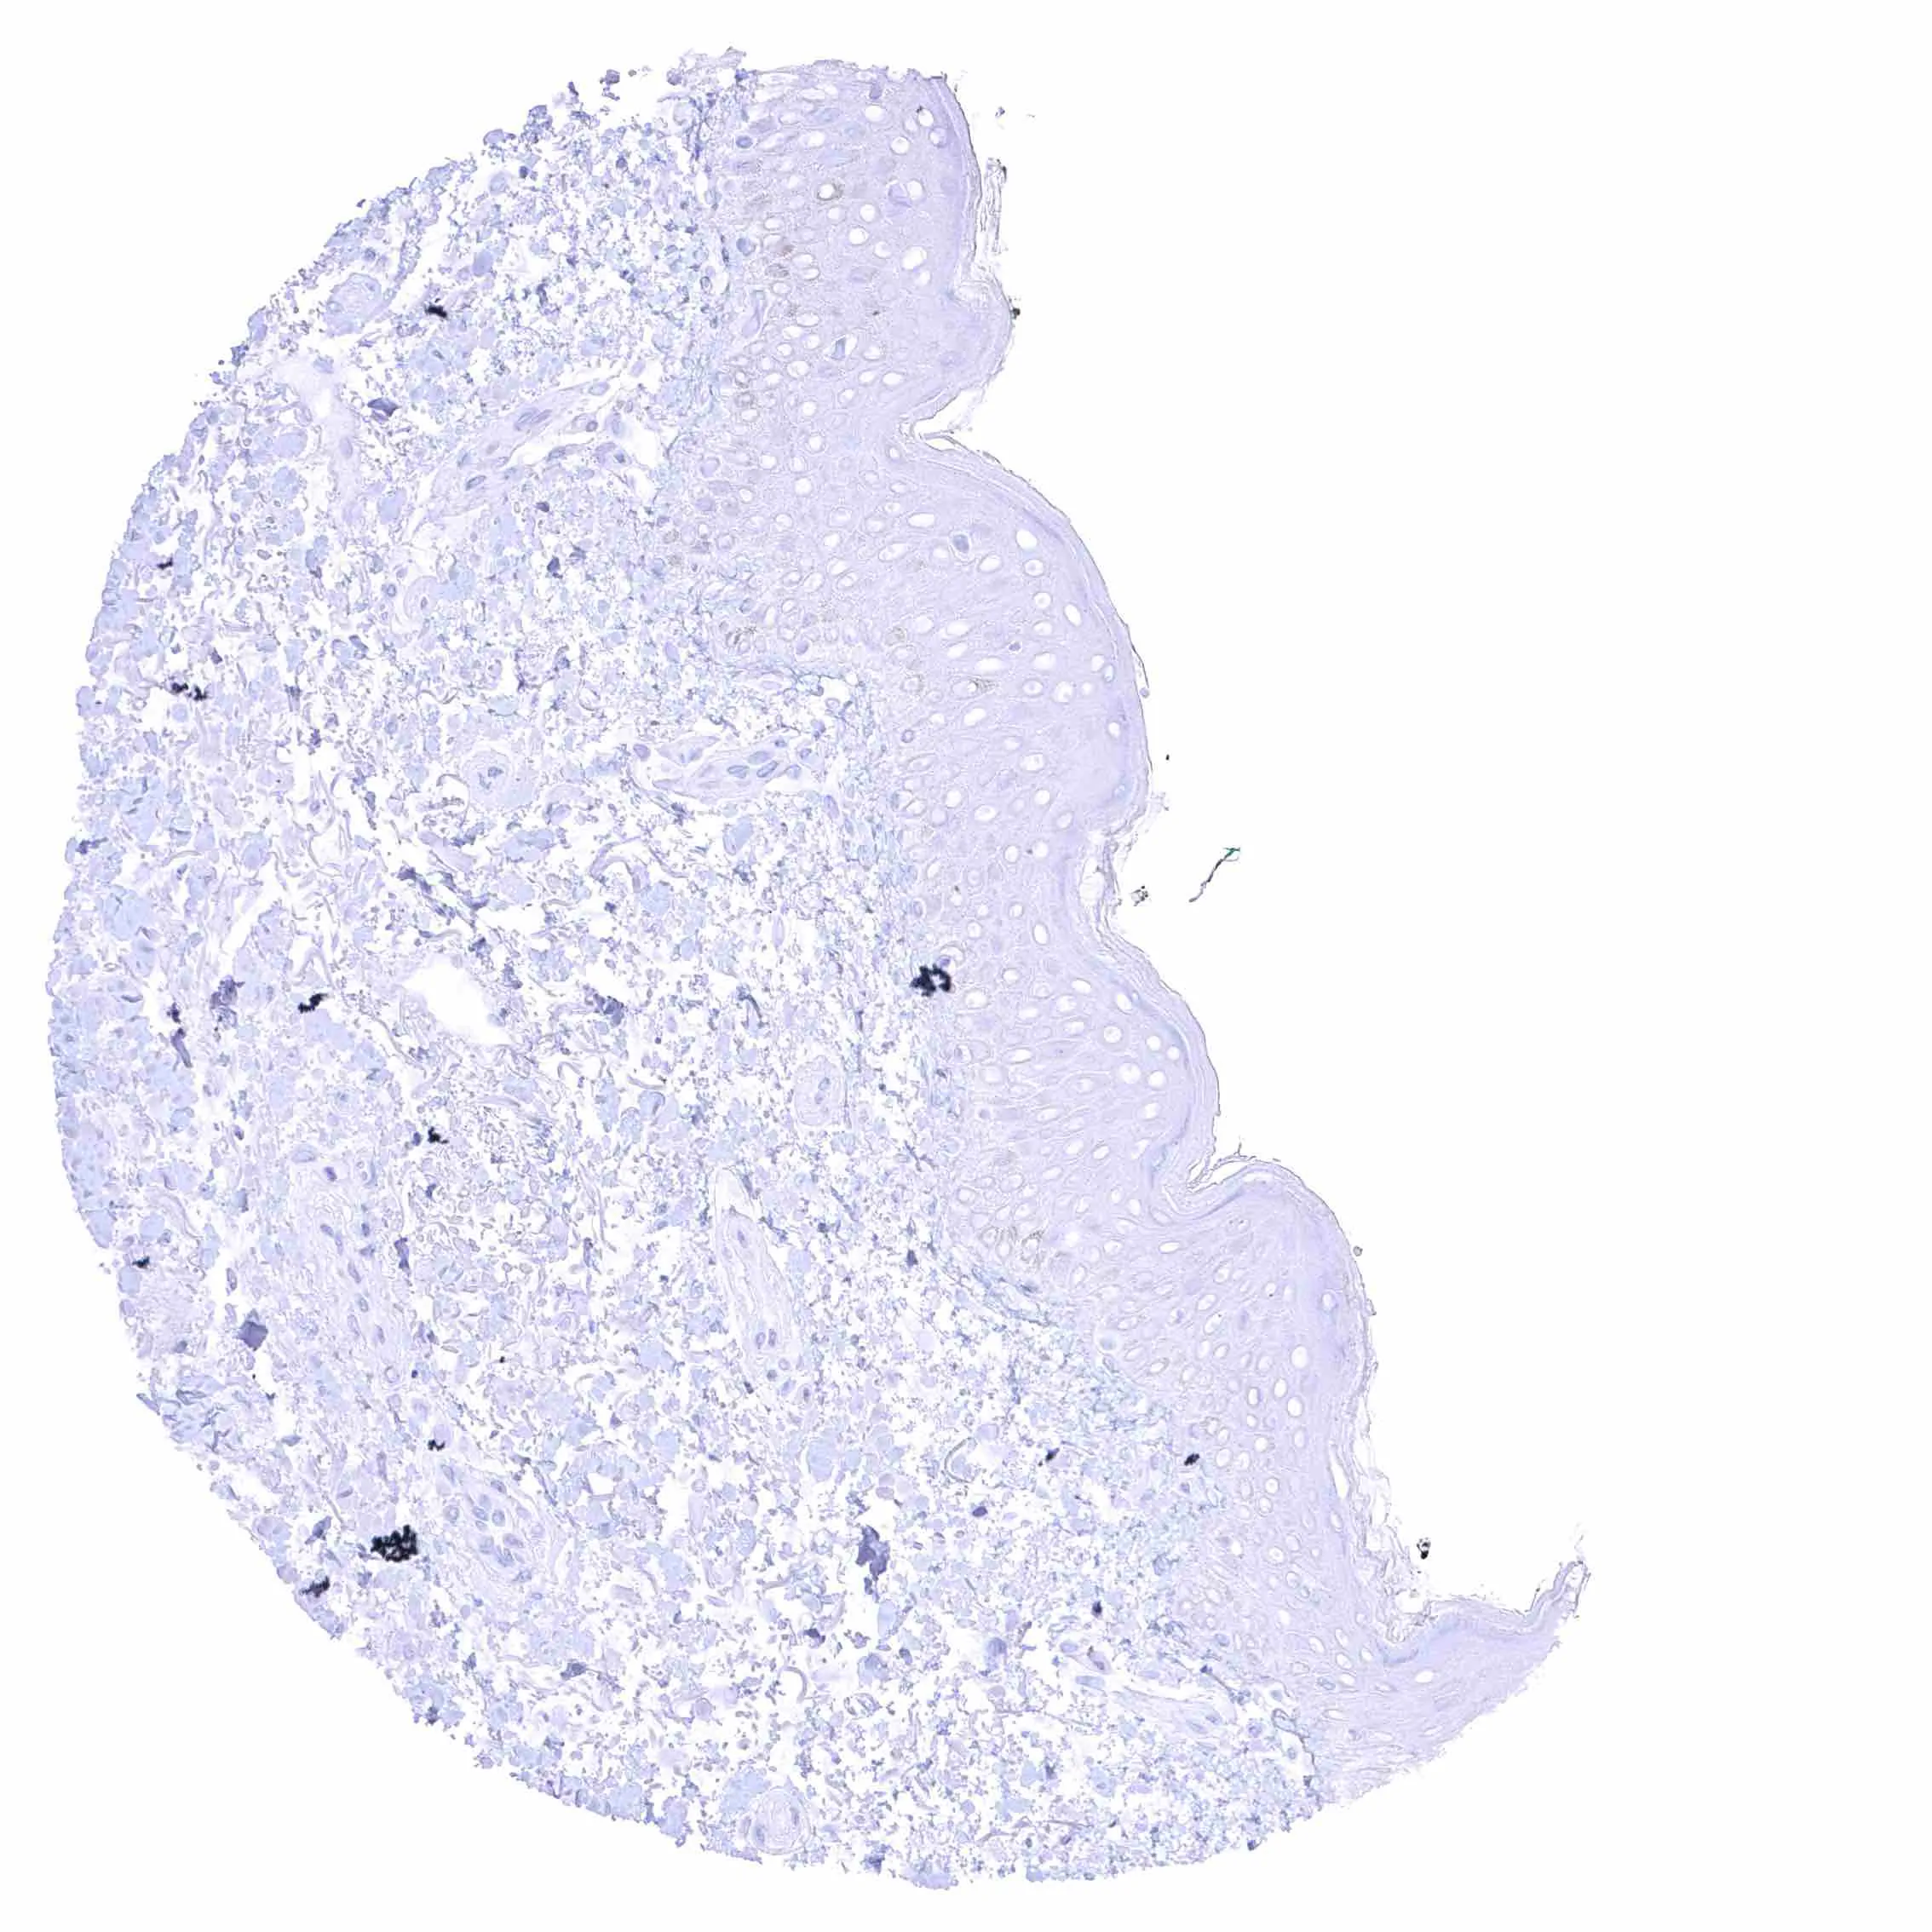

Skin